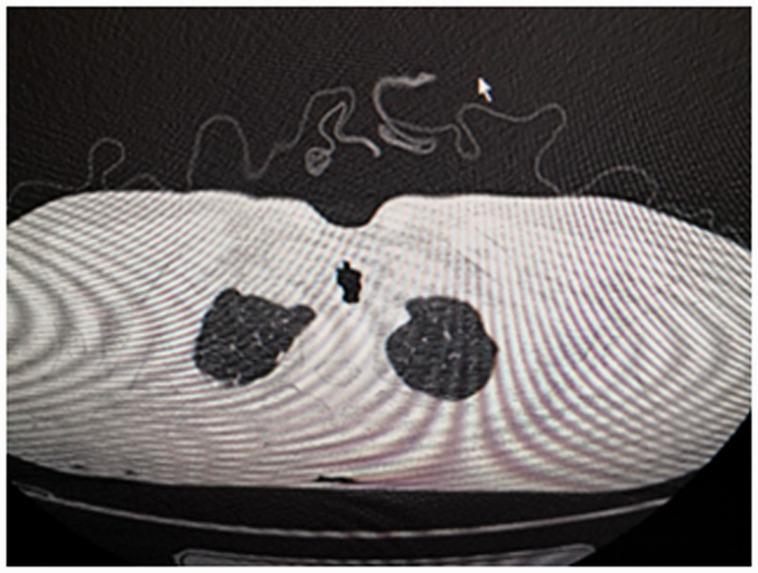

Tracheobronchopathia osteochondroplastica (TO) is a rare disease that may cause unexpected difficult intubation. There is no available consensus on the management of difficult intubation that is associated with TO. A 45-year-old woman was scheduled for modified radical mastoidectomy, canaloplasty, and tympanoplasty under general anesthesia. We encountered significant resistance during tracheal intubation, although the laryngeal view was normal with the video laryngoscope. A fiberoptic bronchoscope was then used to facilitate intubation, and we noted that the trachea was obviously narrowed due to cartilaginous ring hypertrophy. The tracheal tube was fully lubricated with tetracaine gel, and smoothly inserted into the trachea. After the operation, bronchoscopy and a computed tomography (CT) scan were performed to confirm the diagnosis of TO. Fiberoptic bronchoscopy-assisted tracheal intubation is safe and effective choice for the patients in whom subglottic intubation is difficult. CT scan and bronchoscopy might be helpful for preoperative airway assessment. Identifying patients with TO is important to avoid unexpected tracheal intubation impediment. Assessment of the subglottic airway should also be taken seriously.

气道骨软骨病(TO)是一种罕见的疾病,可能导致意外的插管困难。目前对于与 TO 相关的困难插管管理尚无共识。一名 45 岁女性拟在全身麻醉下行改良乳突根治术、鼓室成形术和乳突切开术。尽管视频喉镜下喉视图正常,但我们在气管插管时遇到了明显的阻力。然后使用纤维支气管镜辅助插管,我们注意到气管明显狭窄,是由于软骨环增生所致。充分润滑气管导管的四卡因凝胶,然后顺利插入气管。术后行支气管镜和 CT 扫描以确诊 TO。对于声门下插管困难的患者,纤维支气管镜辅助插管是一种安全有效的选择。CT 扫描和支气管镜检查有助于术前气道评估。识别 TO 患者对于避免意外的气管插管困难很重要。应重视对声门下气道的评估。